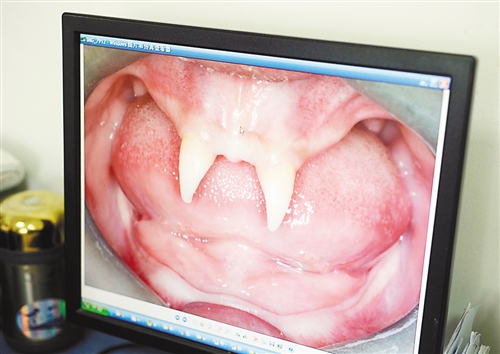

12月18日,16歲的張成(化名)從小到大,只有上顎部分有兩顆牙,看上去更像長(zhǎng)著一對(duì)獠牙。 記者熊明攝

重慶日?qǐng)?bào)訊 每個(gè)人都有牙齒,但對(duì)16歲的張成(化名)來(lái)說(shuō),從小到大,他只有上顎部分有兩顆牙,看上去更像長(zhǎng)著一對(duì)獠牙,這讓他很自卑又易怒。12月18日,在母親的陪同下,他來(lái)到三軍醫(yī)大西南醫(yī)院求助。經(jīng)醫(yī)生檢查,發(fā)現(xiàn)張成患有一種罕見(jiàn)的基因病。

張成是貴州銅仁地區(qū)思南縣人,從生下來(lái)就似乎得了一種怪病,身上毛發(fā)稀少,面部發(fā)育也不好。更奇怪的是,別人家的孩子都長(zhǎng)牙吃東西了,他卻一直長(zhǎng)不出牙齒,最后只在上顎部分冒出兩顆比較突出且對(duì)稱(chēng)的牙齒,看起來(lái)就像一對(duì)獠牙。